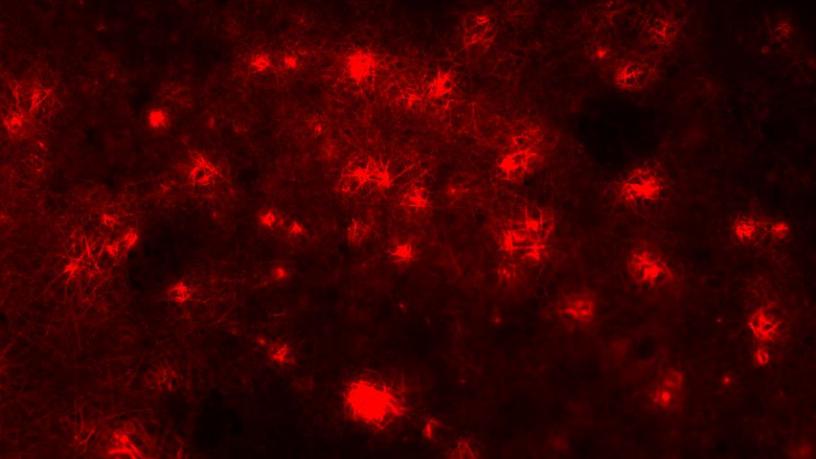

A cartilage-bone construct stained for key extracellular matrix components (red = cartilage , blue = bone)